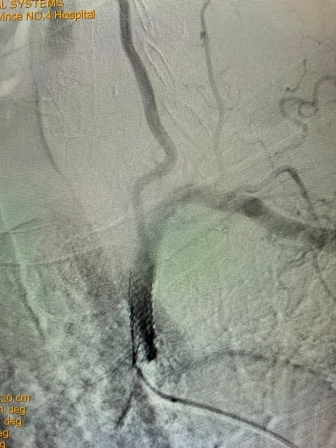

(术前造影) (手术后造影)

该患者是一位79岁老年男性,门诊以“头晕伴走路不稳”主诉入院。既往有高血压、冠心病PCT术后、慢阻肺病史。入院后完善相关检查,行B超检查考虑“左侧锁骨下动脉盗血”,进一步检查DSA全脑血管造影术时发现:“左侧锁骨下动脉闭塞,左侧锁骨下动脉盗血”。为解决患者疾病痛苦及改善其生活质量,神经内科任主任刘蔚玲主持召集专家团队讨论并精心安排,在客座教授刘亚民周密指导下,由神经内科侯有荣副主任医师、孟军鹏主治医师、赵荣健等骨干医生,通过开通闭塞处血管、球囊扩张后置入支架,手术顺利,术后造影显示患者左侧锁骨下动脉血流再通,锁骨下动脉盗血现象消失,血管再开通,患者术后无明显不适、后循环缺血症状消失。手术极大地改善了其生活质量,同时也有效地预防了严重的脑卒中事件的发生。

此例高龄患者、锁骨下动脉闭塞后再通、同时联合椎动脉狭窄病变的同期治疗,其手术复杂、难度大、风险高,神经介入手术创伤小,恢复快,效果立竿见影,其闭塞血管的顺利开通为预防其以后再发生脑梗死奠定了极为重要的基础。该例手术成功完成,再次标志着日韩无码 神经内科(卒中中心)神经介入技术水平更上一层新台阶。(采编 党委宣传部)